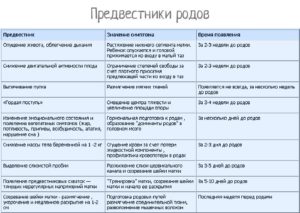

Даже повторнородящие женщины часто пропускают предвестники начинающихся родов, хотя, казалось бы, должны помнить, как начинается процесс появления малыша. Итак, на что следует обратить внимание:

- Перед родами у многих женщин снижается аппетит. Многие будущие мамы отмечают, что вес перед родами может стоять на месте или уменьшаться на несколько килограммов.

- На последних неделях женщина может ощущать тренировочные (ложные) схватки. Когда схватки становятся более ощутимыми, болезненными и продолжаются с регулярным интервалом, пора ехать в роддом. Выпейте таблетку но-шпы, постойте под теплым душем, полежите или посидите в расслабленном состоянии. Если болевые ощущения исчезли, вызывать бригаду скорой помощи рано.

- Перед родами обычно отходит пробка, которая представляет собой густую слизь, часто с примесью кровянистых прожилок. Если вы обнаружили кусочки пробки, это может послужить сигналом приближающихся родов. Но у некоторых женщин после отхождения пробки может пройти какое-то время, прежде чем начнутся роды.

- Часто в последние дни перед родами у будущих мам случается расстройство желудка.

Непосредственно перед родами в организме женщины происходит множество изменений: изменяется состояние связок, мышц, меняется гормональный фон, происходят психологические процессы, которые не могут оставаться незаметными. Это и есть предвестники приближающихся родов.

Предвестники родов в 39 недель у первородящих женщин могут отличаться от процессов, которые происходят в организме женщин, которые готовятся стать мамой в очередной раз.

Физиология повторнородящей женщины отличается тем, что мышцы влагалища и шейка матки менее упругие, а предвестники наступают позже, чем у женщины, которая готовится стать мамой впервые.

Достаточно часто повторные роды начинаются раньше, на 38-39 неделе, в то время, когда первородящие женщины могут ждать до 40-41 недели.

Предвестники родов на 39 неделе у повторнородящих могут быть такими:

- Отхождение слизистой пробки;

- Начало регулярных схваток;

- Опущение живота;

- Снижение веса.

Кроме объективных предвестников, выделяют также субъективные ощущения (нервозность, тревожность, бессонница, эффект гнездования). Но, почувствовав психологический дискомфорт, не стоит ехать в роддом, лучше дождаться достоверных предвестников начинающихся родов (отхождение околоплодных вод, регулярные схватки).

На 39 неделе беременности предвестники родов у первородящих несколько отличаются от симптомов, которые могут наблюдаться у женщин, вынашивающих второго ребенка. Специалисты выделяют такие основные предвестники родов на 39 неделе беременности, которые могут проявляться за неделю до начала родовой деятельности:

- Отхождение слизистой пробки, что выражается увеличением слизи в выделениях.

- Опущение матки, на фоне чего становится легче дышать.

- Снижение массы тела и отсутствие аппетита.

- Учащение ложных позывов к дефекации.

Предвестники родов у повторнородящих отличаются своей скоротечностью. То есть, после появления определенных симптомов, роды могут начаться практически сразу. Быстротечные роды могут представлять угрозу для ребенка. Поэтому, когда тридцать девятый недельный период беременности у повторнородящих женщин связан с тем, что болит живот и тянет поясницу, то лучше сразу обратится в роддом.

Предвестники родов у повторнородящих и первородящих женщин всегда сопровождаются учащением ложных схваток. При этом сильно болит поясница и тянет живот. Если такие симптомы появились, то нужно ожидать начало родов в ближайшее время, а это значит, что необходимо срочно отправляться в роддом.

Наиболее распространёнными предвестниками родов на 39 неделе являются:

- слабые тянущие боли в нижней части живота (тренировочные схватки);

- отхождение слизистой пробки — едва заметные кровянистые выделения из половых путей;

- из сосков может увеличиться количество выделений молозива;

- наблюдается некоторое снижение веса, при этом аппетит будет повышен;

- учащенные позывы к мочеиспусканию и диарея – это еще один из «симптомов» скорого наступления родов;

- появление бессонницы или же наоборот, сонливости;

- наблюдаться боли в пояснице;

- опускание живота и выпячивание пупка. Обычно после этого будущей маме становится гораздо легче дышать;

- снижение веса от 1 кг до 1,5. Такое «похудение» обусловлено уменьшением отечности.

Заметное невооруженным глазом для акушера изменение в организме женщины, которое она не ощущает — это размягчение шейки матки. К 39-ой неделе беременности шейка матки приоткрывается, готовясь к детородному процессу.

Ряд симптомов, появляющихся у большинства беременных за несколько дней до родов, называют предвестниками. Их роль – обозначить готовность организма к серьезному процессу. Женский организм активно готовится к родам для того, чтобы ребенку и роженице было проще преодолеть все трудности рождения.

Предвестники родов при первых родах не всегда заметны, не регулярны и появляются в разное время. Они не дают четкого ориентира о начале процесса и не обязательно появляются все.

К окончанию третьего триместра появление предвестников не случайно. Оно связано с изменениями, происходящими с организмом беременной. Например, размягчение шейки матки влияет на характер выделений; опустившееся дно матки корректирует осанку беременной; а повышенные эстрогены влияют на аппетит, настроение и стул.

Выработка эстрогенов к 39неделе существенно увеличивается, а уровень прогестерона, который все 9 месяцев блокировал сокращения матки, падает. Активизируются простагландины, стимулирующие начало родовой деятельности.

- Опускается живот (если это не случилось ранее). У впервые рожающих женщин этот предвестник заметнее, чем у тех, кому предстоят повторные роды. Это связано с большей эластичностью мышц живота. За положение живота отвечают мышцы передней брюшной стенки.

- Уменьшение массы тела. Это происходит буквально за 2-3 дня до родов. Потери веса могут достигать 3 кг. Организм освобождается от лишней жидкости, выводя ее с мочой. Особенно заметна потеря веса, если у беременной наблюдались отеки. Этот предвестник возникает в связи с тем, что организм готовится минимизировать кровопотерю при родах, если она случится. Механизм таков: снижается объем жидкостной составляющей крови. Таким образом организм делает кровь гуще, повышая показатели ее свертываемости: вероятная кровопотеря при родах будет меньше. Вторая причина выведения лишней жидкости – это отсутствие расхода на генез амниотической жидкости. Не требуется больше и наращивать объем крови для работы в системе мама-ребенок. Случается, что перед родами организм избавляется от жидкости не только с мочой, но и с жидким стулом.

- Самый яркий предвестник родов – это тренировочные схватки. Матка пробует себя, готовится к родовой деятельности. Предвестниковые сокращения аритмичны. Могут длиться несколько недель и, как и сокращения Брекстона-Хикса, призваны подготавливать матку к работе во время родов. Подобные тренировки помогают созреванию шейки матки, расширяя и укорачивая ее. До 37 недели схватки не являются предвестниковыми. Не путайте тренировочные схватки с тонусом матки и настоящими родовыми схватками. Различия существенны, хотя возникают все эти сократительные активности по одному принципу: мышцы матки напрягаются, становясь плотными, четко очерчивают ее контур, возникает тяжесть в области крестца и внизу живота. Предвестниковые схватки короткие и относительно безболезненные. Наблюдаются до 6 раз в сутки, способствуют активизации кровообращения и обеспечивают ребенку доставку большего объема питательных веществ. Тренировочные сокращения проходят сами или смягчаются при приеме дротаверина или постановке расслабляющей свечки, при массаже, принятии душа. Тонус матки – это длительное, болезненное, не проходящее напряжение, угрожающее плоду. Родовые схватки, в отличие от тренировочных, регулярны, их интенсивность и частота нарастают. От них невозможно отвлечься.

- О степени созревания шейки матки рассказать может только акушер. Во время беременности длина шейки – 3 см. Пред родами она уменьшается до сантиметра-полутора. В родах шейка, представляющая собой мышечную трубку, должна окончательно растянуться и раскрыться. Короткая шейка – признак скорых родов. Длинная шейка на 39 неделе считается незрелой. О состоянии шейки судят на основе влагалищного исследования: зрелая шейка расположена в центре, легко растягивается, мягкая, с проходимым цервикальным каналом.

- В целом, при сочетании нескольких видов предвестников с нарушением аппетита, возникновением расстройства кишечника, можно говорить о близости родов.